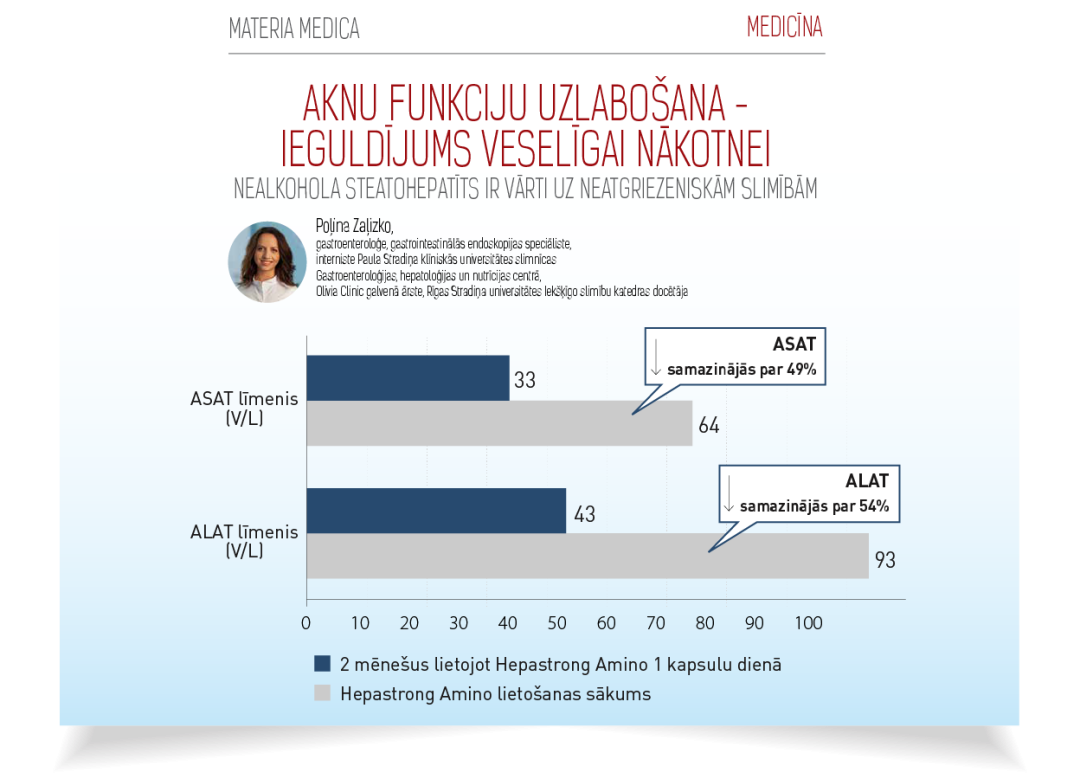

2018. gadā tika veikts novērojums, kas ilga 2 mēnešus hepatologu un ģimenes ārstu uzzraudzībā. Novērojuma laikā pacienti ar paaugstinātiem ALAT un ASAT rādītājiem lietoja Hepastrong Amino 1 kapsulu dienā.

Pēc 2 mēnešu lietošanas, pacientiem ievērojami samazinājas aknu enzīmu rādītāji, kas liecina par efektivitāti.

ASAT samazinājās par 49%

ALAT samazinājās par 54%

Atsauce: Zaļizko, P. MATERIA MEDICA, 2021